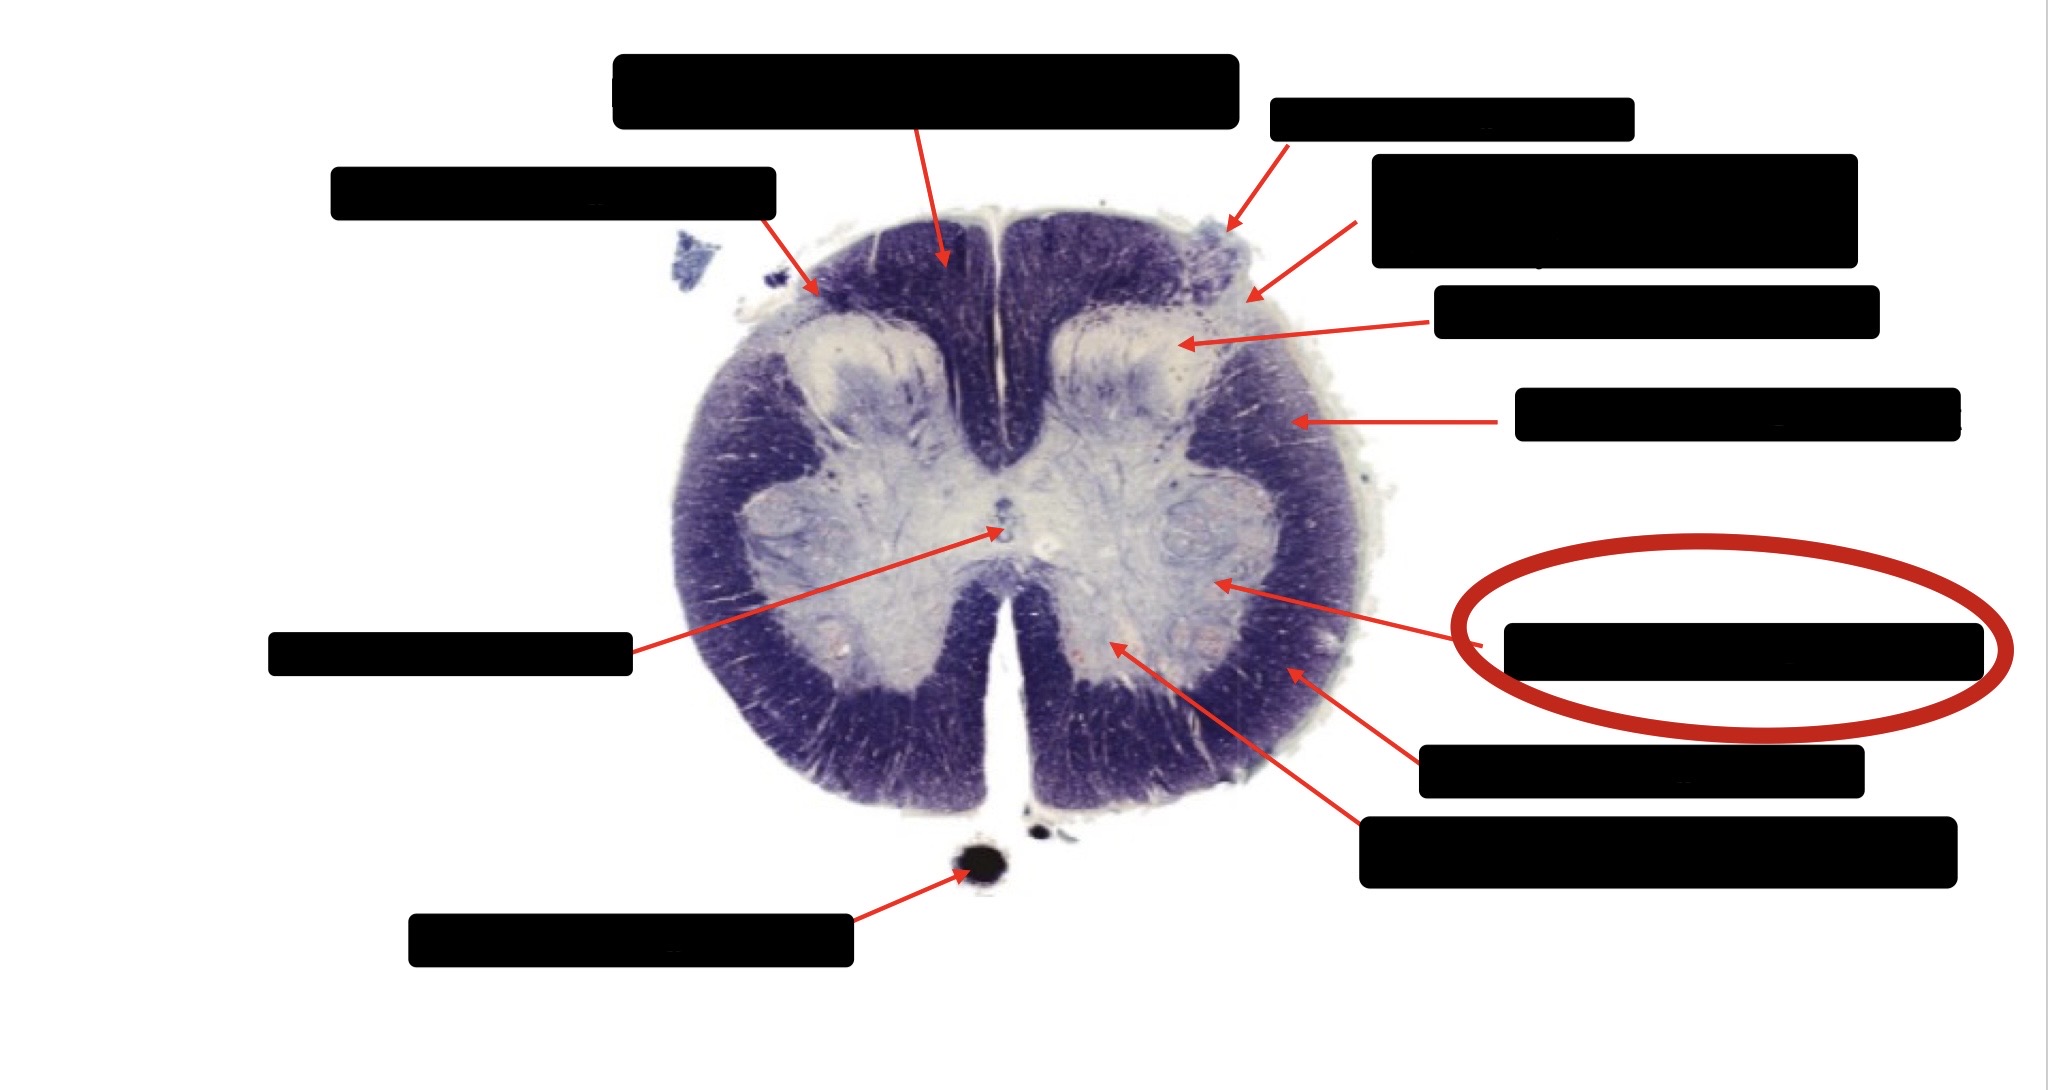

Anterior Spinal Artery

Denticulate Ligament

Ventral Root

Dorsal Root

Posterior Column Fasciculus Gracilis

Large Fiber Entry Zone

Central Canal